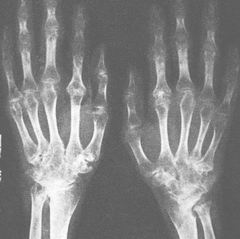

5.X線檢查之表現可助診斷:早期關節囊腫脹,爾後出現骨端出現圓形或半圓形邊緣銳利的穿鑿樣缺損。晚期關節間隙變窄,關節邊緣骨質增生,關節強直,可伴有脫位和病理性骨折。

(四)慢性關節炎期由急性發病至轉為慢性關節炎期平均11年左右,關節出現僵硬畸形、運動受限。30%左右病人可見痛風石和發生腎臟合併症以及輸尿管結石等。晚期有高血壓、腎腦動脈硬化、心臟梗塞。少數病人死於腎功能衰竭和心血管意外。繼發性痛風病程相似,繼發於血液病、糖原儲存病的間歇期較短。血尿酸檢查增高,最高達20mg%(正常:男7mg%,女6mg%)。偏光顯微鏡發現關節滑液中吞噬了尿酸鹽結晶的白血球。急性期時白血球增高,血沉加快。X線檢查顯示關節軟骨下骨的穿鑿樣破壞以及局部的骨質疏鬆、腐蝕或皮質斷裂,關節間隙狹窄和邊緣性骨質增生。痛風結石可為鈣化陰影。